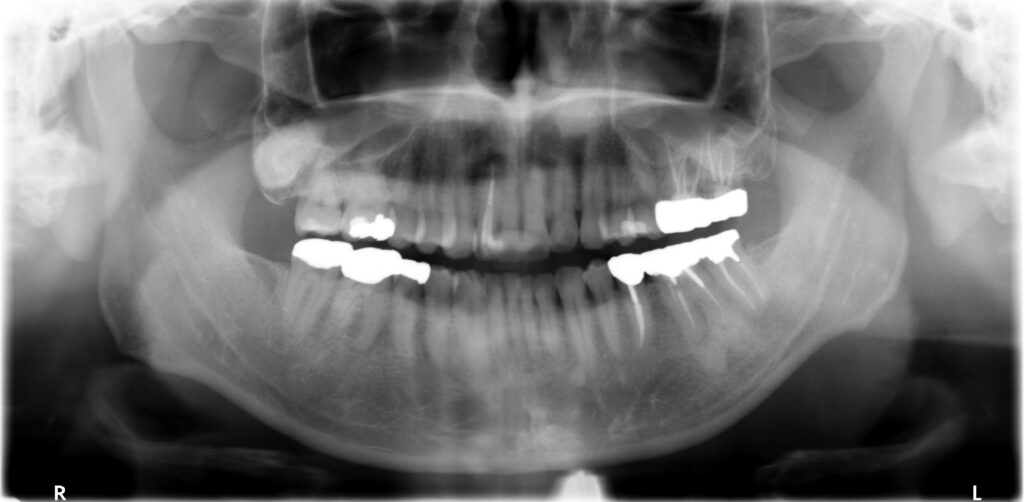

術前パノラマレントゲン写真

- パノラマ術前所見―向かって右下一番奥の歯(左下7番)の根っこの先が黒くなっている骨透過像を呈する。